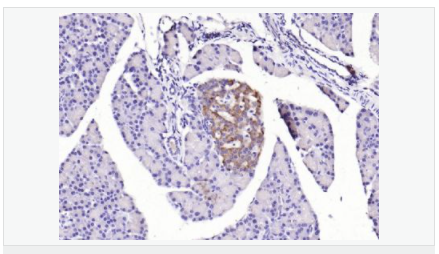

Lgr5基因(Wnt細胞信號系統(tǒng))是一種G蛋白偶聯(lián)受體,已經(jīng)被確定為幾種成年組織和癌癥中干細胞的一個獨特標記。Lgr5最初是在結(jié)腸癌細胞中發(fā)現(xiàn)的,有報道稱:在惡化前的小鼠腺瘤中也有發(fā)現(xiàn),這說明Lgr5很可能也是其他組織成體干細胞和癌癥干細胞的標志物。